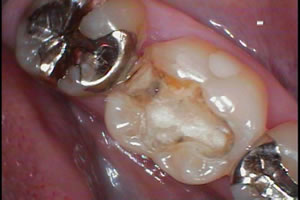

歯医者をやっていると毎日のように「古い銀歯が取れたんですけど~!」

といった訴えで来院される患者様が多いです!

もちろんそのまま接着して終了の場合もありますが、、、

よく見ると、、、

接着剤の下に黒い虫歯が、、、

作りかえた方が良い場合もあります!!! |

虫歯の深い部分を修復材料でベースしてあるのですが、

その下に虫歯が、、、

ようするに銀歯を接着していたセメント(接着剤)が腐食して、隙間ができ虫歯になって銀歯が外れたようです!

この場合は虫歯も含めてきれいに除去して、新しいベース材料にやりかえてから、新しい銀歯の型どりとなります! |